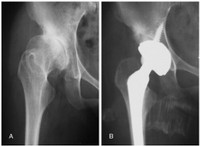

Quello che è certo però è che se non viene identificata precocemente, la lussazione dell’anca porta a una grave disabilità: il bambino zoppica per il risalimento della testa femorale sulla faccia esterna del bacino e più tardi l’adulto manifesterà molto presto i segni dell’artrosi rendendo necessario il ricorso alla protesi in età anticipata rispetto alla media della popolazione (fig. 3).

Fig. 3